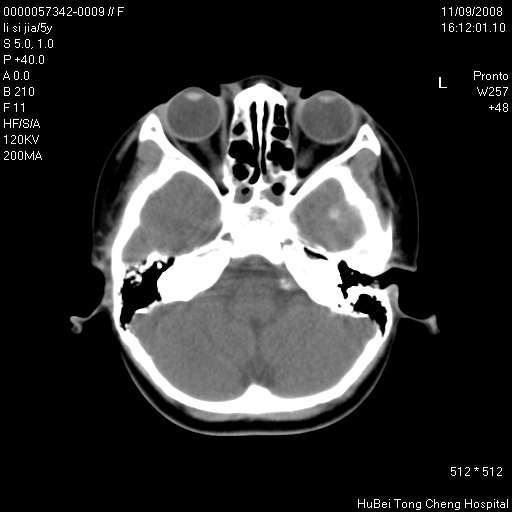

患儿 女,5岁。鼻塞、流涕2年余。

临床诊断:慢性副鼻窦炎?

副鼻窦ct轴位平扫(层厚、层距均为5mm),图像如下:

双侧上颌窦\\筛窦及蝶窦内均可见多量软组织密度影,结合病史支持考虑慢性全鼻窦炎

双侧上颌窦、筛窦及蝶窦内均可见粘膜增厚,结合病史支持考虑慢性全付鼻窦炎,腺样体肥大。